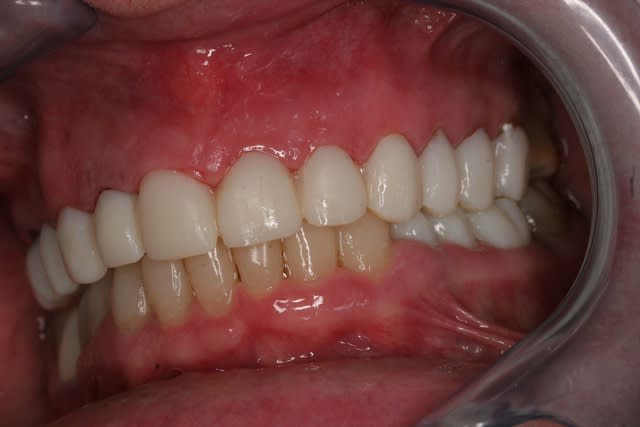

Et voila la pose , pour les habitants du nouveau monde c'est très coloré, pour les Franchouillard c'est naturel... perso je m'en fout la patiente est toute joilleuse et j'ai pas honte de moi, j'ferais encore mieux dés qu'on m'en donneras l'occasion.

Fin 002 j3hb61 - Eugenol

Fin 005 htq1ba - Eugenol

Fin 006 dpgjbp - Eugenol

Fin 008 owjdyz - Eugenol

Fin 007 lhlszz - Eugenol